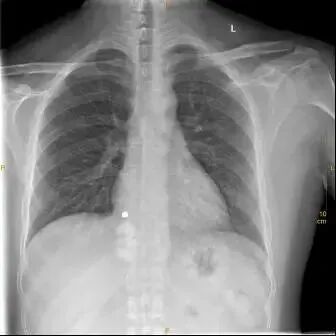

这是一张标准胸片

一张合格的胸片是不允许有任何体外异物的,因为任何异物的存在都会影响诊断。